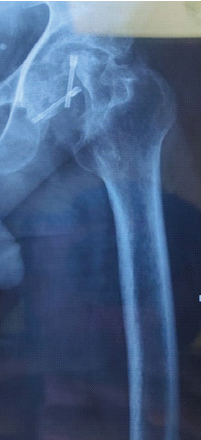

Aneurysmal Bone Cyst Presenting as a Pathological Subtrochanteric Femur Fracture in an Adolescent: A Case Report

Chandrashekhar R Rai , Sandeep V Gavhale , Vijaysing Chandele , Alok P Yadav , Chinmay S Torne , Vishal B Karpe

………………………………p.89-93